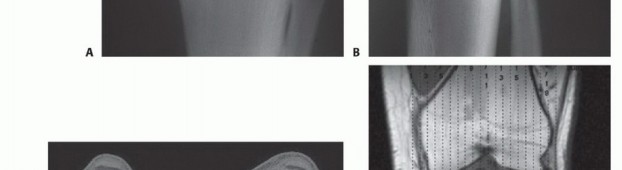

- التصوير بالرنين المغناطيسي (MRI): يُعتبر الأداة الأكثر أهمية لتحديد مدى انتشار الورم داخل العظم، وفي الأنسجة الرخوة المحيطة، وعلاقته بالأوعية الدموية والأعصاب. يُساعد في تحديد هوامش الاستئصال الجراحي.

- التصوير المقطعي المحوسب (CT Scan): يُستخدم لتقييم التدمير العظمي بشكل أفضل، وتحديد وجود أي نقائل في الرئتين أو أجزاء أخرى من الجسم.

- تصوير الأوعية ثنائي المستوى (Digital Subtraction Angiography - DSA): في بعض الحالات، يُستخدم لتقييم إمداد الدم للورم وعلاقته بالأوعية الرئيسية، خاصة عند التخطيط للجراحات المعقدة.